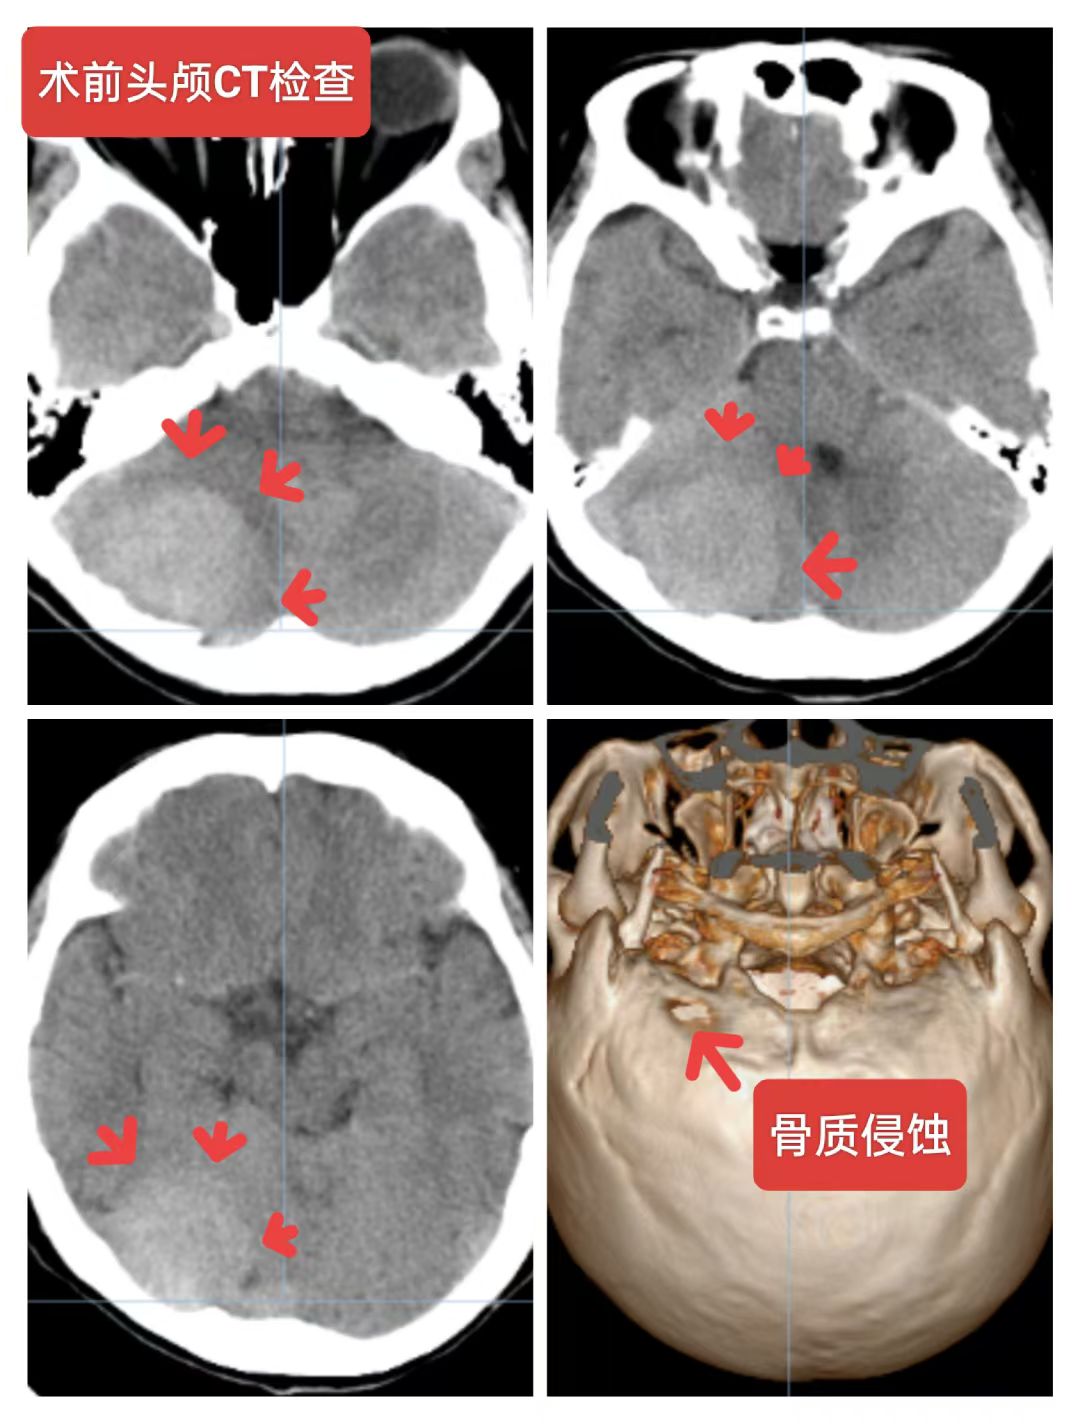

右侧小脑半球脑膜瘤:患者56岁女性,间断性头痛一年,加重一周入院,头颅核磁提示:右侧小脑半球脑膜瘤,压迫横窦,侵蚀天幕向幕上生长,术中见肿瘤质地韧,肿瘤突破硬脑膜,局部骨质破坏,横窦壁有侵蚀,窦壁少量残留,侵蚀硬脑膜及肿瘤全切除,取人工硬脑膜修补缝合,目前患者恢复良好。